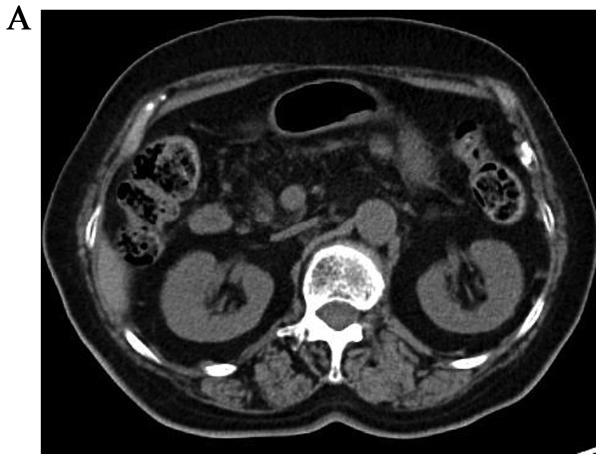

Intraductal papillary mucinous neoplasms (IPMNs) are characterized by the papillary proliferation of atypical mucinous epithelial cells in the pancreatic ductal system. There are two recurrence patterns following resection of IPMNs: Metachronous multifocal occurrence of IPMNs, and distinct pancreatic ductal adenocarcinoma (PDAC) in the remnant pancreas. Several recent studies investigated the development of distinct PDAC during follow-up evaluation of IPMNs and the incidence rate ranged from 4.5 to 8%. Thus, IMPNs may be a good predictor for the early detection of PDAC during observation or after the resection of IPMNs. We herein report the rare case of a patient who underwent resection of PDAC that developed in the remnant pancreas 13 years after distal pancreatectomy with splenectomy for IPMNs. PDAC may develop in the remnant pancreas after pancreatectomy for IPMNs; thus, careful long-term follow-up with periodic surveillance, at least every 6 months, is warranted.

导管内乳头状黏液性肿瘤(IPMNs)的特征是胰腺导管系统中不典型黏液上皮细胞的乳头状增殖。IPMNs切除术后有两种复发模式:IPMNs的异时多灶性发生,以及残余胰腺中出现不同的胰腺导管腺癌(PDAC)。最近的几项研究调查了IPMNs随访评估期间不同PDAC的发生情况,发病率在4.5%至8%之间。因此,IMPNs可能是在观察期间或IPMNs切除后早期检测PDAC的良好预测指标。我们在此报告了一例罕见病例,该患者因IPMNs行远端胰腺切除术加脾切除术后13年,残余胰腺发生了PDAC并接受了切除。IPMNs行胰腺切除术后,PDAC可能在残余胰腺中发生;因此,有必要进行仔细的长期随访,至少每6个月进行一次定期监测。